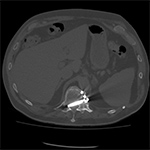

| 70 year-old man with history of L1 and L3 injury and T11-L3 spinal fusion in the 1990's. Recent worsening of chronic lower back pain. Standard radiographs (left two images) show a vertebral body corpectomy cage at T12-L3 with placement of a left lateral side plate at the same levels. There are two proximal screws at T12, one of which enters the spinal canal as shown on subsequent CT (right two images). There are two distal screws at L3, the most distal of which enters the L3-4 disk space (lateral radiograph). |